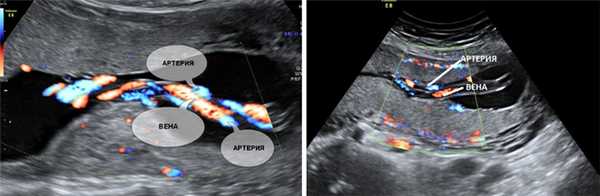

5. Единственная артерия пуповины.

Нормальная пуповина состоит из трех сосудов - две артерии и одна вена. Иногда вместо двух артерий в пуповине формируется только одна артерия и одна вена, таким образом, в пуповине определяется всего два сосуда. Данное состояние считается пороком развития пуповины, однако этот порок не оказывает никакого влияния на послеродовое состояние ребенка и его дальнейшее развитие.

Иногда единственная артерия пуповины выявляется у абсолютно нормальных плодов; после рождения ребенка данный факт не оказывает никакого влияния на его дальнейшее развитие. Иногда единственная артерия пуповины сочетается с пороками сердечно-сосудистой системы плода, поэтому при выявлении единственной артерии пуповины проводится детальный осмотр анатомии плода и, в частности, сердечно-сосудистой системы. При отсутствии других пороков развития единственная артерия пуповины в состоянии обеспечить адекватный кровоток плода. Несколько чаще единственная артерия пуповины выявляется у плодов с синдромом Дауна и другими хромосомными болезнями. Однако этот маркер относится к «малым» маркерам синдрома Дауна, поэтому выявление только единственной артерии пуповины не повышает риск наличия синдрома Дауна и не является показанием к проведению других диагностических процедур. Единственная артерия пуповины иногда приводит к возникновению задержки внутриутробного развития плода. В связи с этим при обнаружении единственной артерии пуповины рекомендуется дополнительное УЗИ в 26-28 недель беременности, и плановое в 32-34 недели. Если отставание размеров плода от срока беременности или нарушение кровотока в сосудах плода и матки не выявлено, то диагноз задержки развития плода исключен.

Что делать при выявлении единственной артерии пуповины у плода?

Выявление только единственной артерии пуповины не повышает риск наличия синдрома Дауна и не является показанием к консультации генетика и проведению других диагностических процедур. Необходимо контрольное УЗИ в 26-28 и 32 недели беременности для оценки темпов роста плода и оценки его функционального состояния.